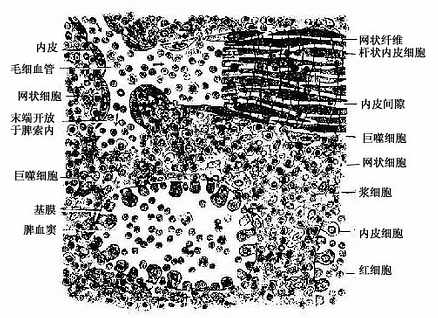

图9-20 脾索与脾血窦模式图

脾索(splenic cord):由富含血细胞的索状淋巴组织构成,脾索在血窦之间相互连接成网,索内含有T细胞、B细胞和浆细胞,以及许多其他血细胞和巨噬细胞,是脾进行滤血的主要场所。脾索内各类细胞的分布并不均匀一致。当中央动脉末端分支进入脾索成为髓微动脉时,其周围有薄层密集的淋巴细胞,在鞘毛细血管周围则有密集的巨噬细胞,至毛细血管末端开放于脾索时含血细胞和巨噬细胞较多,而不含血管的脾索部分则散在的淋巴细胞和浆细胞相对较多。

脾血窦(splenic sinus):是一种静脉性血窦,宽约12~40μm,形态不规则,相互连接成网。窦壁由一层长杆状的内皮细胞平行排列而构成。内皮细胞之间常见许多0.2~0.5μm宽的间隙,脾索内的血细胞可经此穿越进入血窦(图9-21,9-22)。内皮外有不完整的基膜及环行网状纤维围绕,故血窦壁如同一种多孔隙的栏栅状结构。在血窦的横切面上,可见杆状内皮细胞沿血窦壁呈点状排列,较粗大的内皮细胞断面中可见有细胞核,并突入管腔(图9-19)。血窦外侧有较多的巨噬细胞,其突起可通过内皮间隙伸向窦腔。